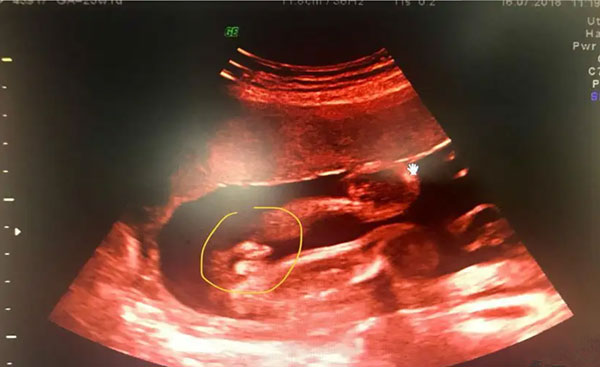

B超有两点基本是男孩--当女性成功的受孕后,在孕期中可能会有很多的孕妈妈非常好奇宝宝的性别是什么,为了想要早点知道腹中胎宝宝的性别,大家可谓是八仙过海,各显神通啊。但是据说,通过B超有两点基本就可以确认是男孩了,那么具体是怎样的呢,一起来了解下吧。

第一点、看B超图中的胎儿的生殖特征

1、如果又双腿之间有三个亮的,说明是男孩儿,因为对应的这三个亮点是男宝宝的生殖特征。

2、当在做B超的过程中,显示有三条线是一样的,或者是胎儿双腿间密密麻麻的黑线、黑杠,对应的是女宝宝的***,是女孩的生殖特征。

注意:医生在检查的时候通常会避开胎儿的生殖器,一般情况下是看不到这么明确的男女标志。